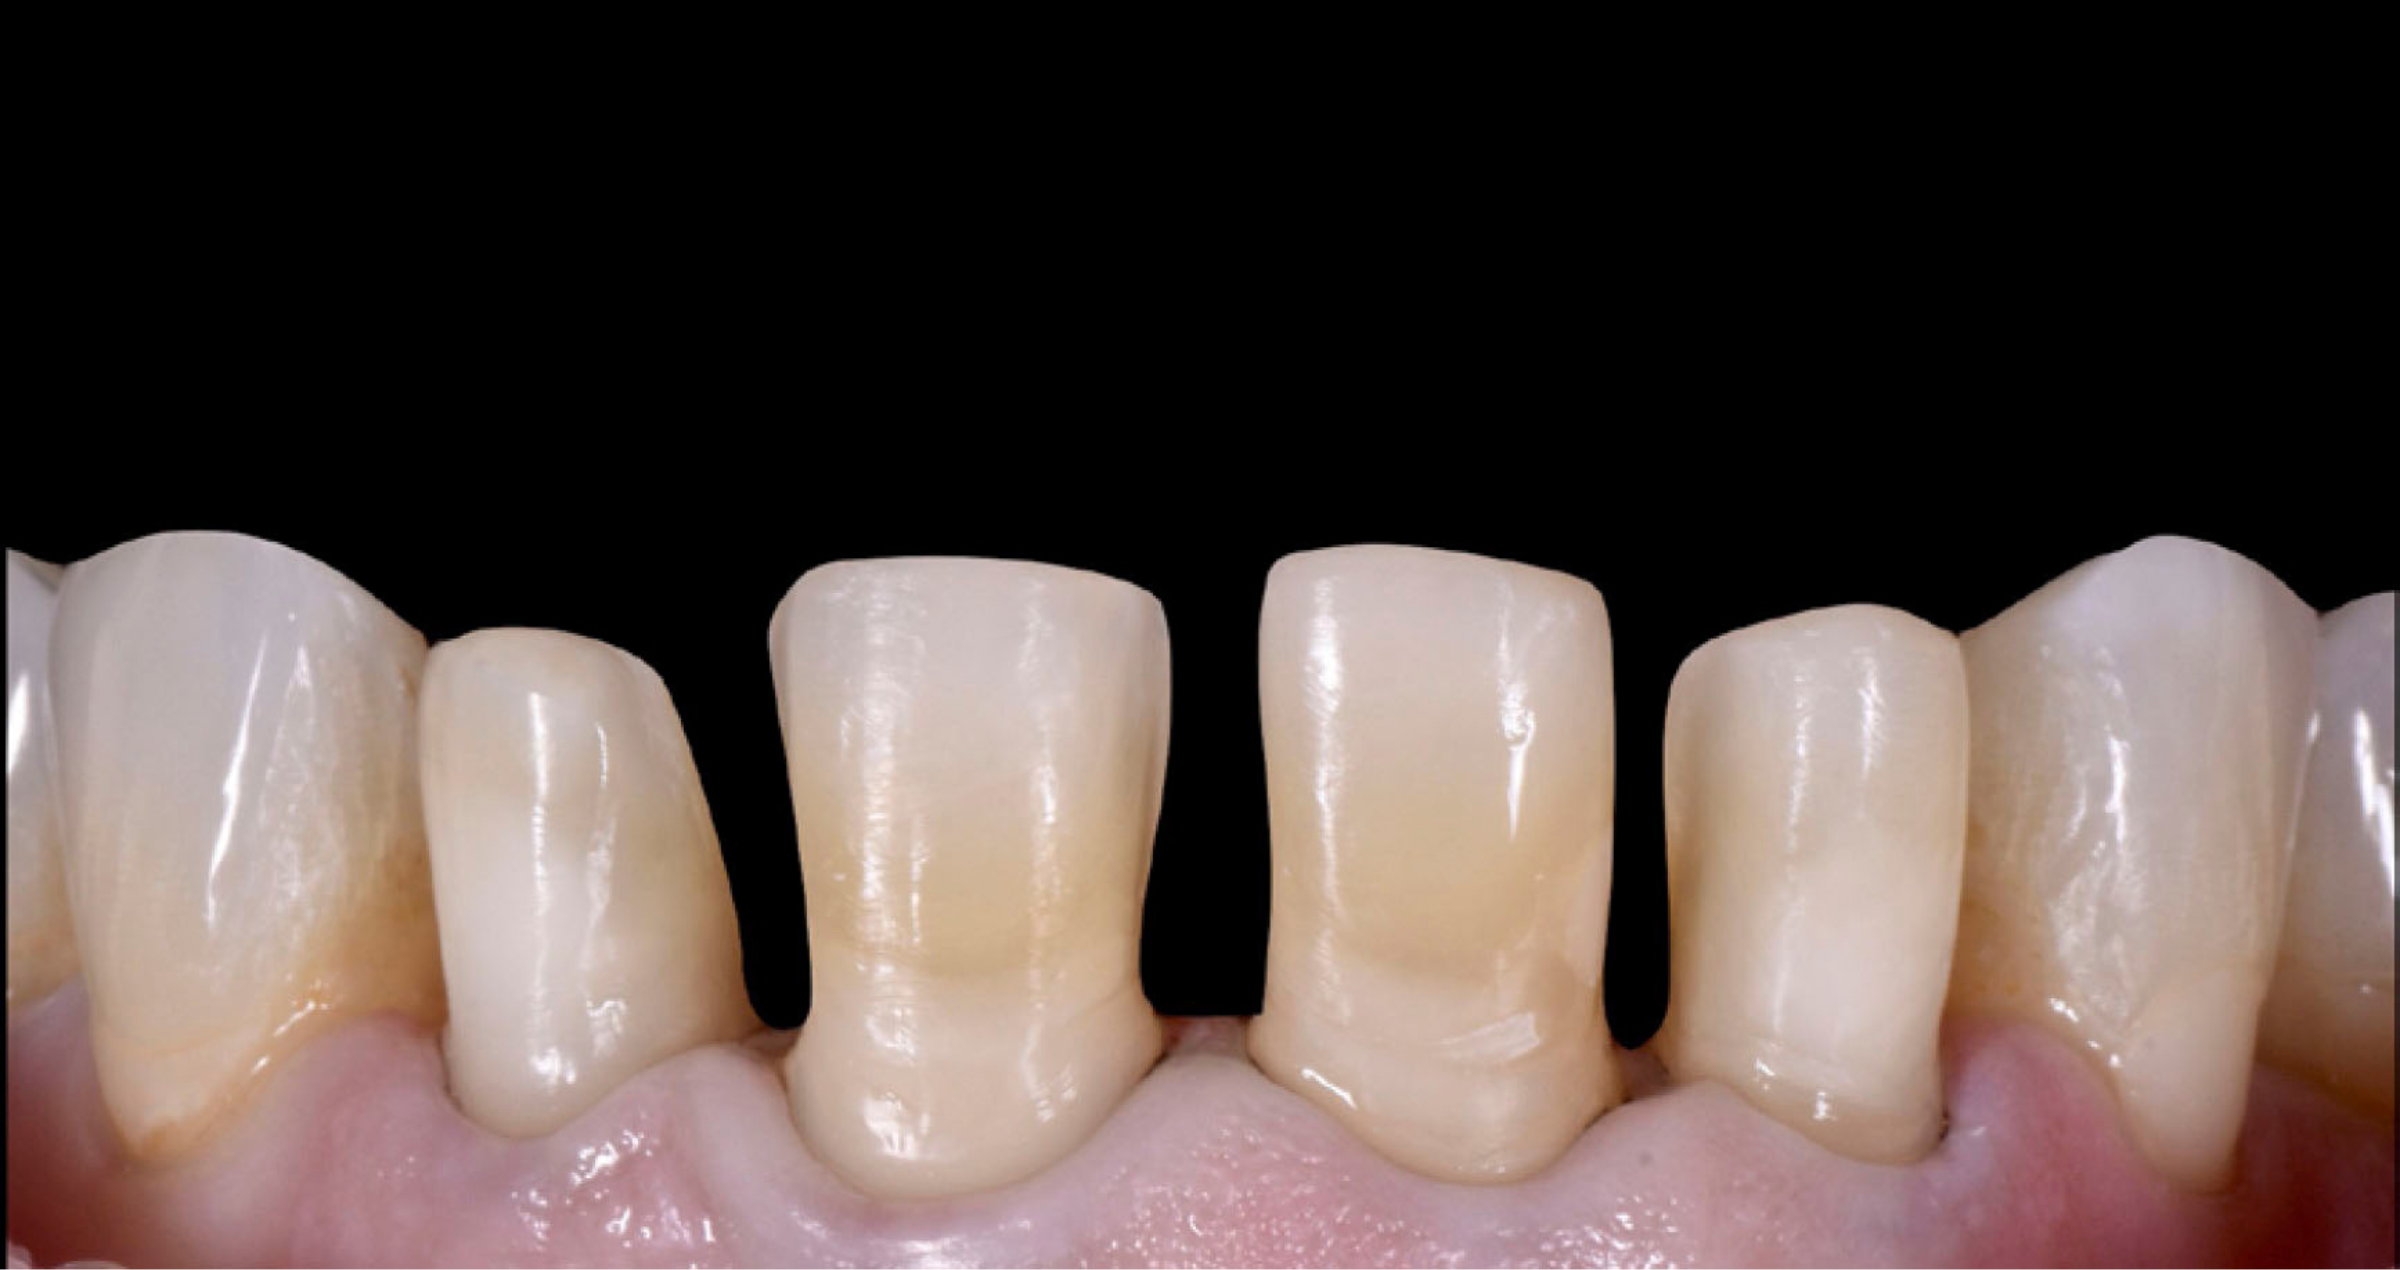

Una paziente di 52 anni si è presentata con l’obiettivo di migliorare l’estetica degli incisivi centrali superiori, caratterizzati da restauri compositi datati e spazi interdentali residui dovuti a pregressa malattia parodontale. Dopo aver ottenuto la stabilità parodontale, si è optato per la realizzazione di quattro faccette in KATANA™ Zirconia.

Fig. 1: Situazione iniziale della paziente con richieste di ripristino estetico funzionale degli elementi dentali frontali superiori.